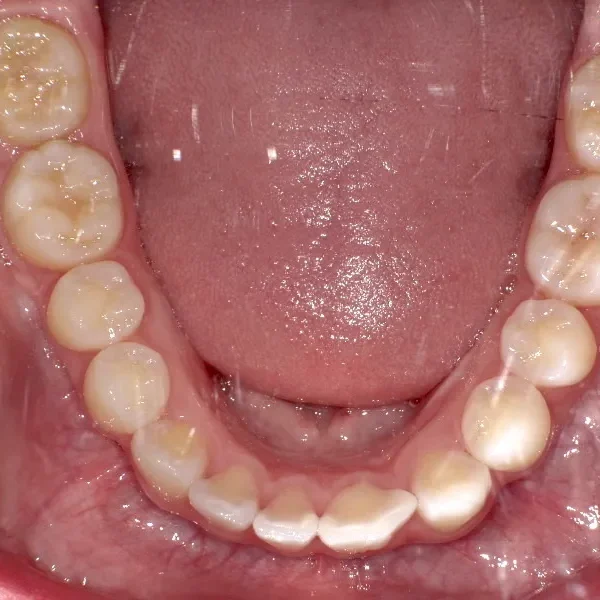

上下ガタガタで、下の歯は癒合歯(2本がくっついて1本の歯)です。

治療前と治療後で下の歯の銀歯がなくなっています。

これは銀歯の第1大臼歯を抜いて第2大臼歯、第3大臼歯の親知らずを使いました。

コルチコトミーという矯正法で歯根への負担を軽減しながら治療しました。

治療回数71回、3年5ヶ月の治療期間で矯正治療を終了しました。